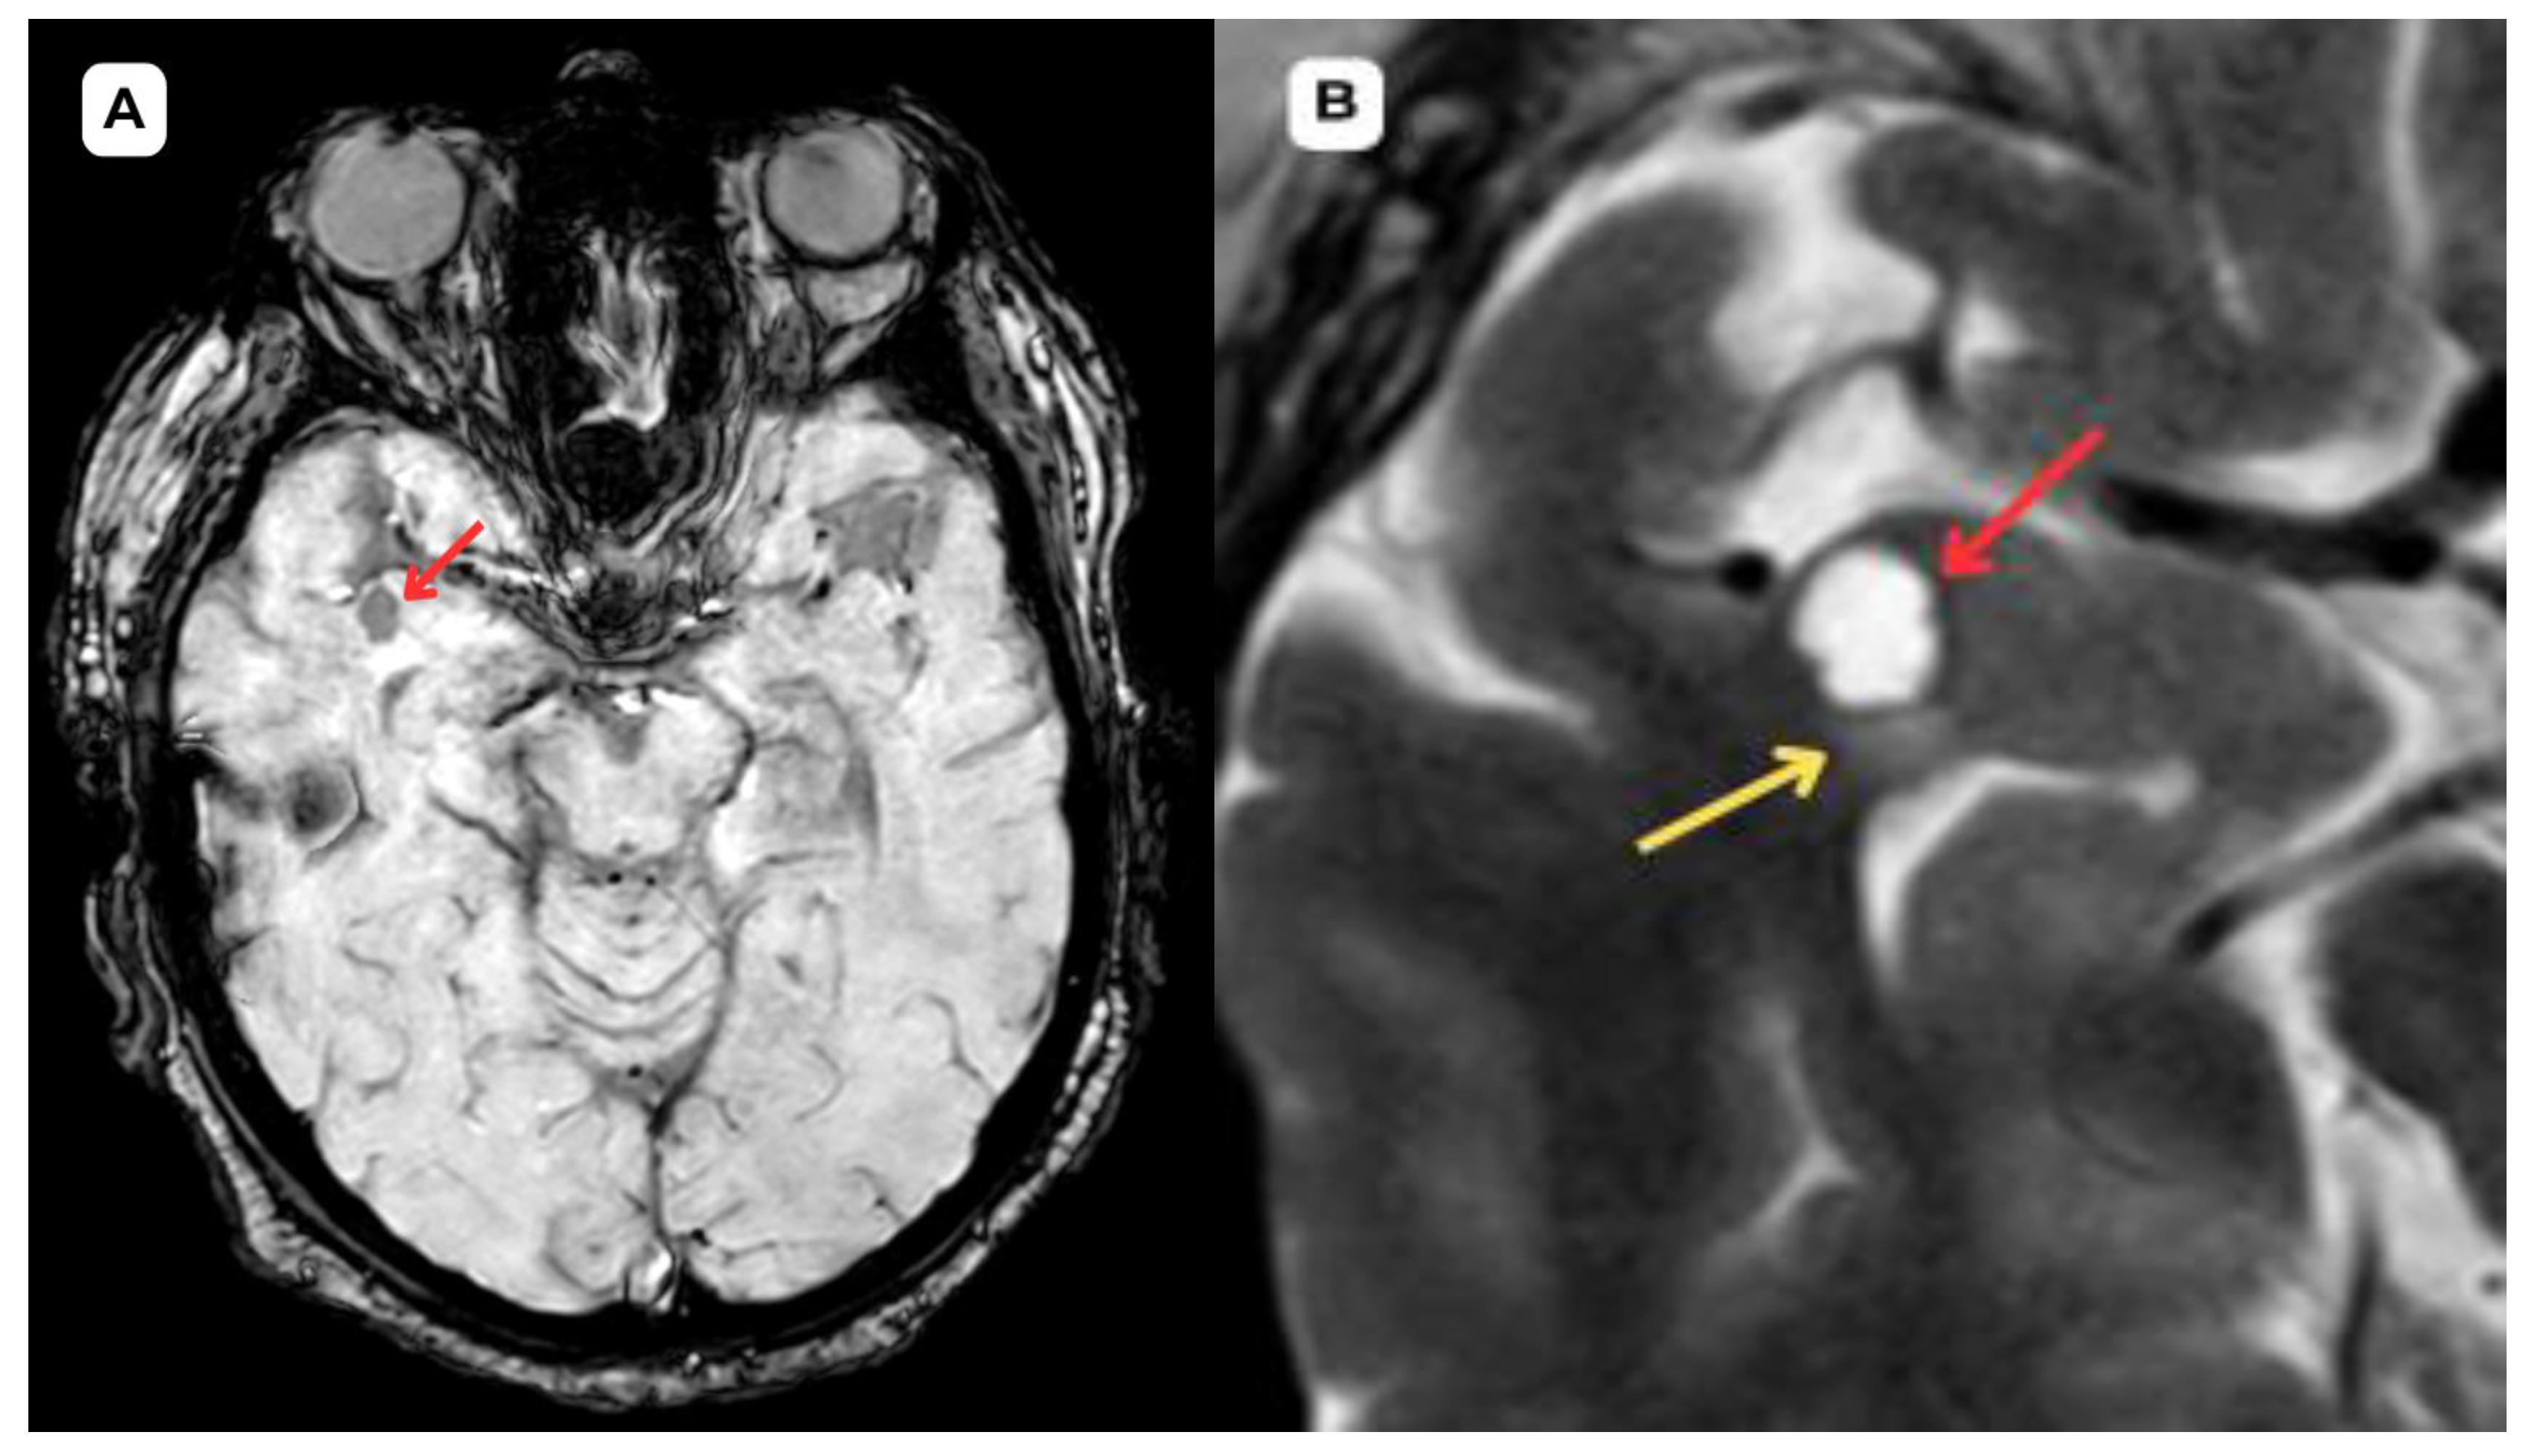

Figure 5. Accompanying second patient: brain MRI of a 67-year-old male. (A): Susceptibility weighted imaging (SWI) axial. A cystic lesion (red arrow) is seen without any hemosiderin or blood products surrounding it. (B): T2-weighted sequence axial, zoomed in, demonstrates better visualization of the very minimal perifocal edema/gliosis (yellow arrow) around the cystic lesion (red arrow) in the white matter. Red arrow—opercular (type IV) perivascular space, yellow arrow—surrounding edema.